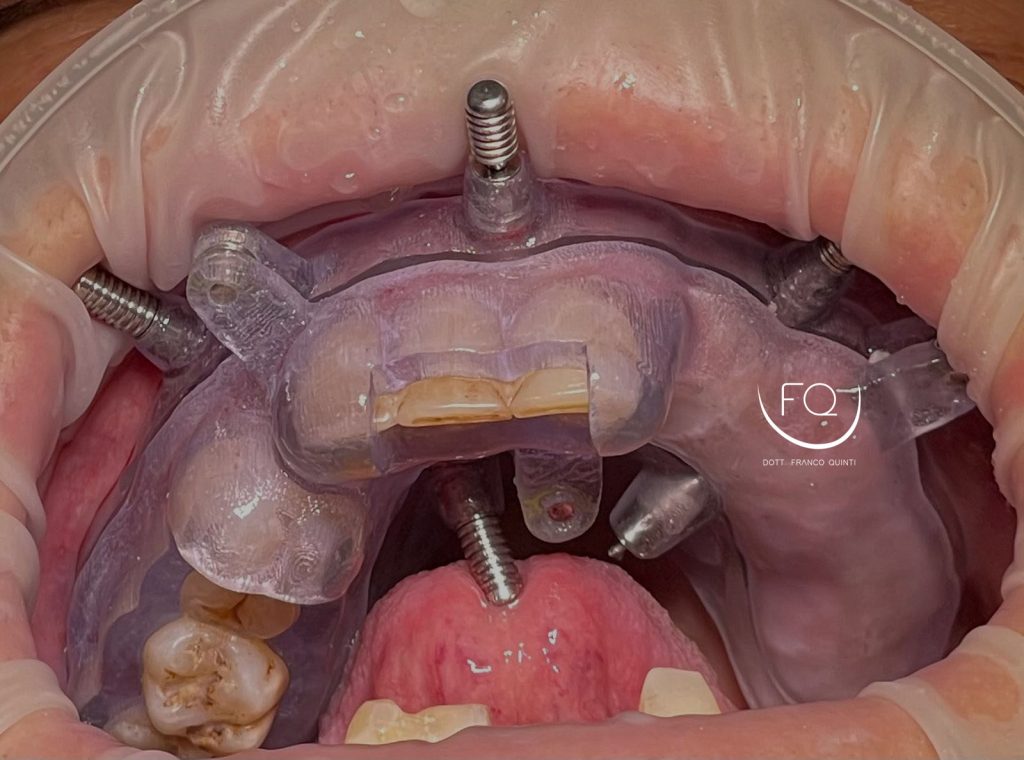

Questa settimana vi presento un caso di chirurgia computer guidata dell’arcata superiore realizzato con dime scomponibili con esecuzione contestuale di un carico immediato.

Nelle prossime settimane vi mostrerò dei brevi video di questo caso relativi alla scomposizione e alla progettazione delle dime chirurgiche.